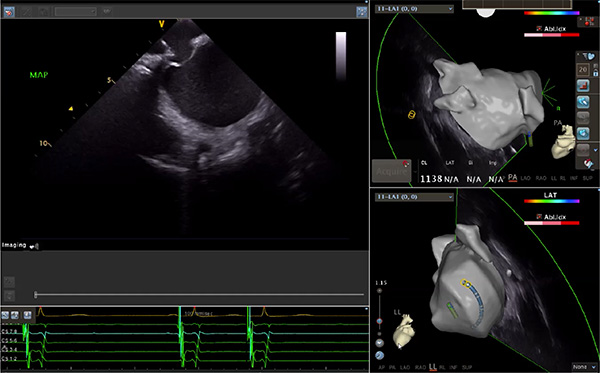

超聲心動圖技術(shù)包括常規(guī)經(jīng)胸超聲(TTE)、經(jīng)食管超聲(TEE)、心腔內(nèi)超聲(ICE)、超聲聲學(xué)造影(MCE)、三維超聲心動圖等,ICE是一種新興技術(shù)——將微型的換能器安裝在心導(dǎo)管的尖端,經(jīng)由外周血管輸送至心腔內(nèi)部,換能器發(fā)射聲波,對心臟及其鄰近組織進(jìn)行實時高質(zhì)量成像和(或)血流動力學(xué)測定的超聲成像技術(shù)。基于不同的技術(shù)原理,心腔內(nèi)超聲導(dǎo)管被分為兩類:機(jī)械旋轉(zhuǎn)式超聲導(dǎo)管和相控陣超聲導(dǎo)管。目前,臨床上主要應(yīng)用的是相控陣超聲導(dǎo)管,ICE成像通過術(shù)者旋轉(zhuǎn)導(dǎo)管及操縱導(dǎo)管手柄上的兩個旋鈕來完成。

隨著心腔內(nèi)超聲的應(yīng)用更廣,性能也在逐漸優(yōu)化,已從二維成像轉(zhuǎn)變?yōu)?strong>三維成像,極大增強(qiáng)了引導(dǎo)及可視化能力。二維心腔內(nèi)超聲支持雙平面或三平面成像,可顯示兩個或三個不同的平面視圖,但醫(yī)生需將這些圖像在腦海中重新構(gòu)建為三維解剖結(jié)構(gòu)。三維心腔內(nèi)超聲則可直接呈現(xiàn)三維解剖結(jié)構(gòu)圖,便于醫(yī)生更輕松地開展手術(shù)。按照產(chǎn)品發(fā)展方向,預(yù)計心腔內(nèi)超聲還將向更清晰、精準(zhǔn)、多功能等方向發(fā)展。